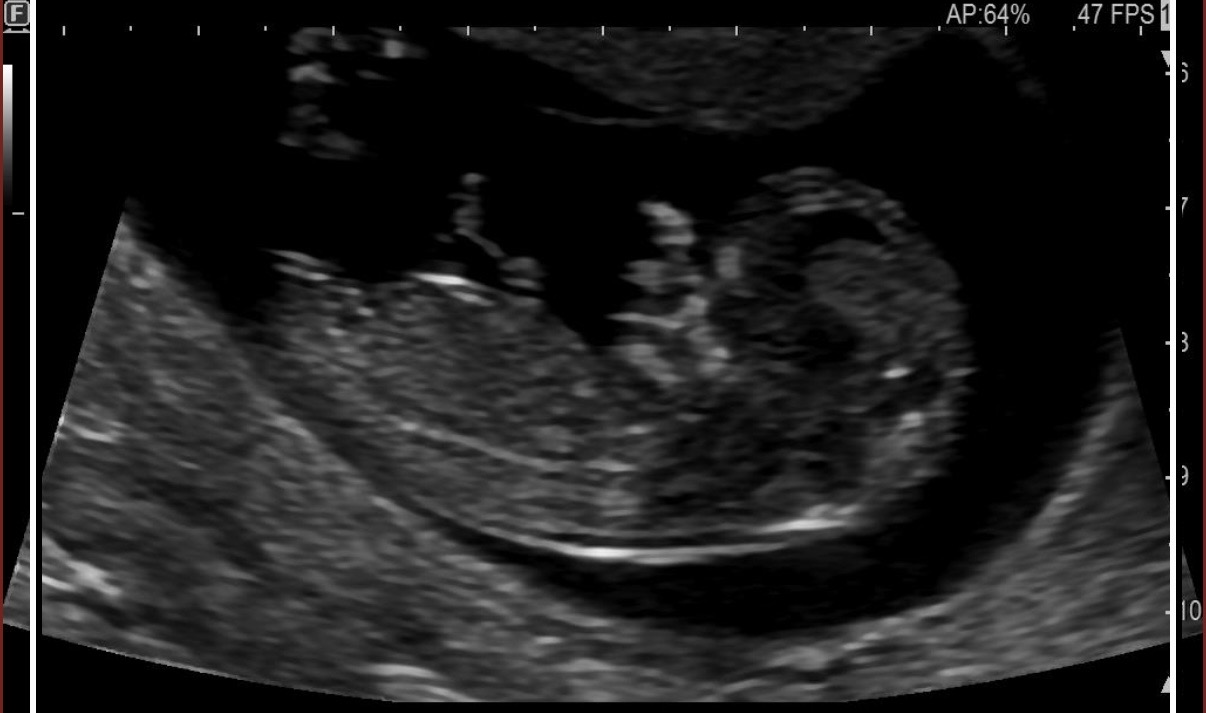

Kız iki çizgi var

cinsel organı düz 80 derece aşağına bence kız

Bence erkekkk

Benim keseme benziyor bence erkek